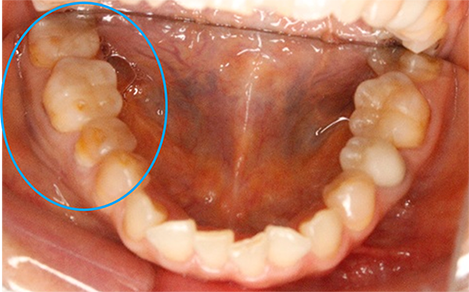

しかし、よく観察してみると、右下の奥歯が異常に削れているのがわかります。

上の写真のように、象牙質と呼ばれる第二層目(歯の内面の黄色い部分)が露出していますが、これは異常なことです。ちなみに、外側の第一層目はエナメル質です。

人間の歯は1年間で約0.03mmしか咬耗しないと言われており、エナメル質自体も厚みが2mm以上ある人が大半です。つまり、まだ50歳の段階で歯の内面が露出するほど削れてしまっているというのは、何か特別な要因が潜んでいることが考えられます。

今回の患者様は、歯が溶けやすくなる食品を頻繁に摂取する習慣もなく、逆流性食道炎(胃酸が頻繁に込み上げてくる病気)でもなかったので、噛み合わせに問題があると判断しました。